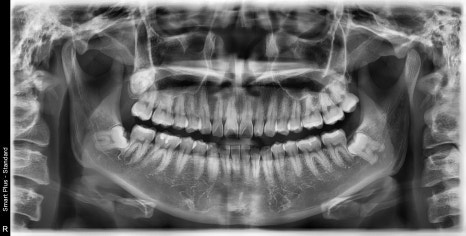

| 발치 전 | 발치 후 |